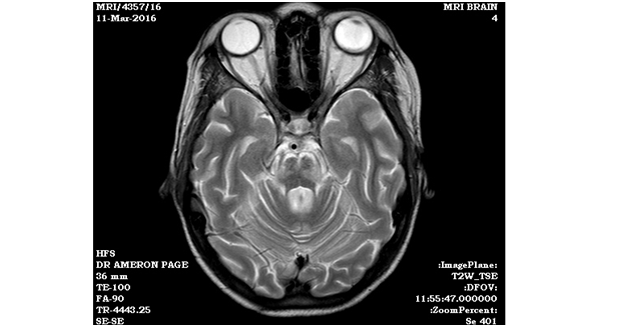

MRI revealed demyelinating lesions in the central pontine region consistent with osmotic demyelination syndrome (thin black arrow, Figure 1).  The 24-hour urine free cortisol was 415 mcg/dL (normal range 10-100 mcg/d). Overnight 8mg dexamethasone suppression test was 2.5 mcg/dL, which confirmed the diagnosis of Cushing disease. Her neuroleptic medications were held, and over the next two weeks she regained alertness and lucidity.

Figure 1A & B MRI revealed demyelinating lesions in the central pontine region.